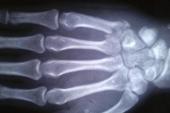

- 1、目的:评价微型钢板在治疗掌骨、跖骨、指骨骨折中的疗效。2、在租借考文垂期间,亨德森遭遇了脚部第五节跖骨骨折,随后于2009年四月回归桑德兰。3、外纵弓由跟骨、骰骨和外侧的两个跖骨构成.4、跖骨痛

- 1、辛辣味呛得我直翻白眼,牙根直发麻,手指骨节痒,想揍他一顿。2、目的:评价微型钢板在治疗掌骨、跖骨、指骨骨折中的疗效。3、骨龄的评估其实就是通过分析远、中、近指骨,桡骨和尺骨等特定骨的特征来与模板